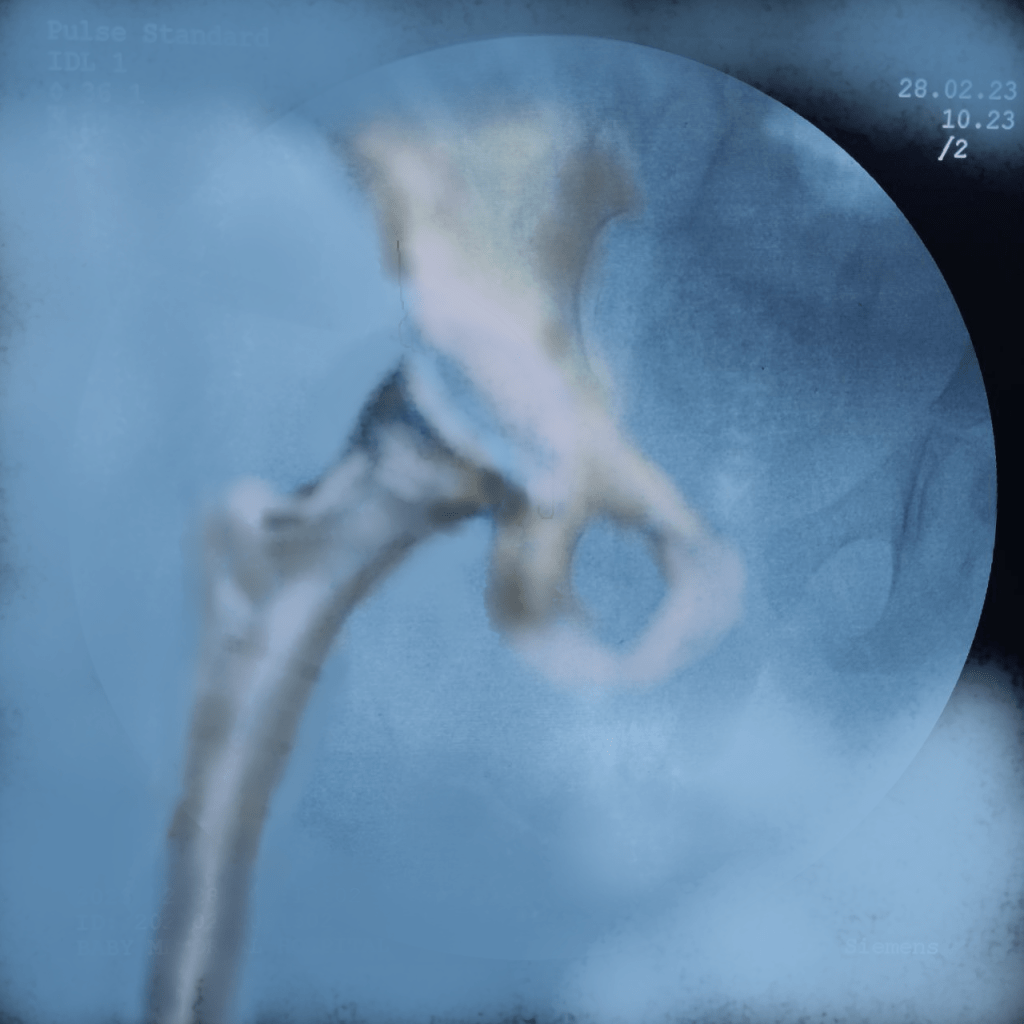

The Derotation osteotomy improved the coverage but we still have to decide about the acetabular procedure.